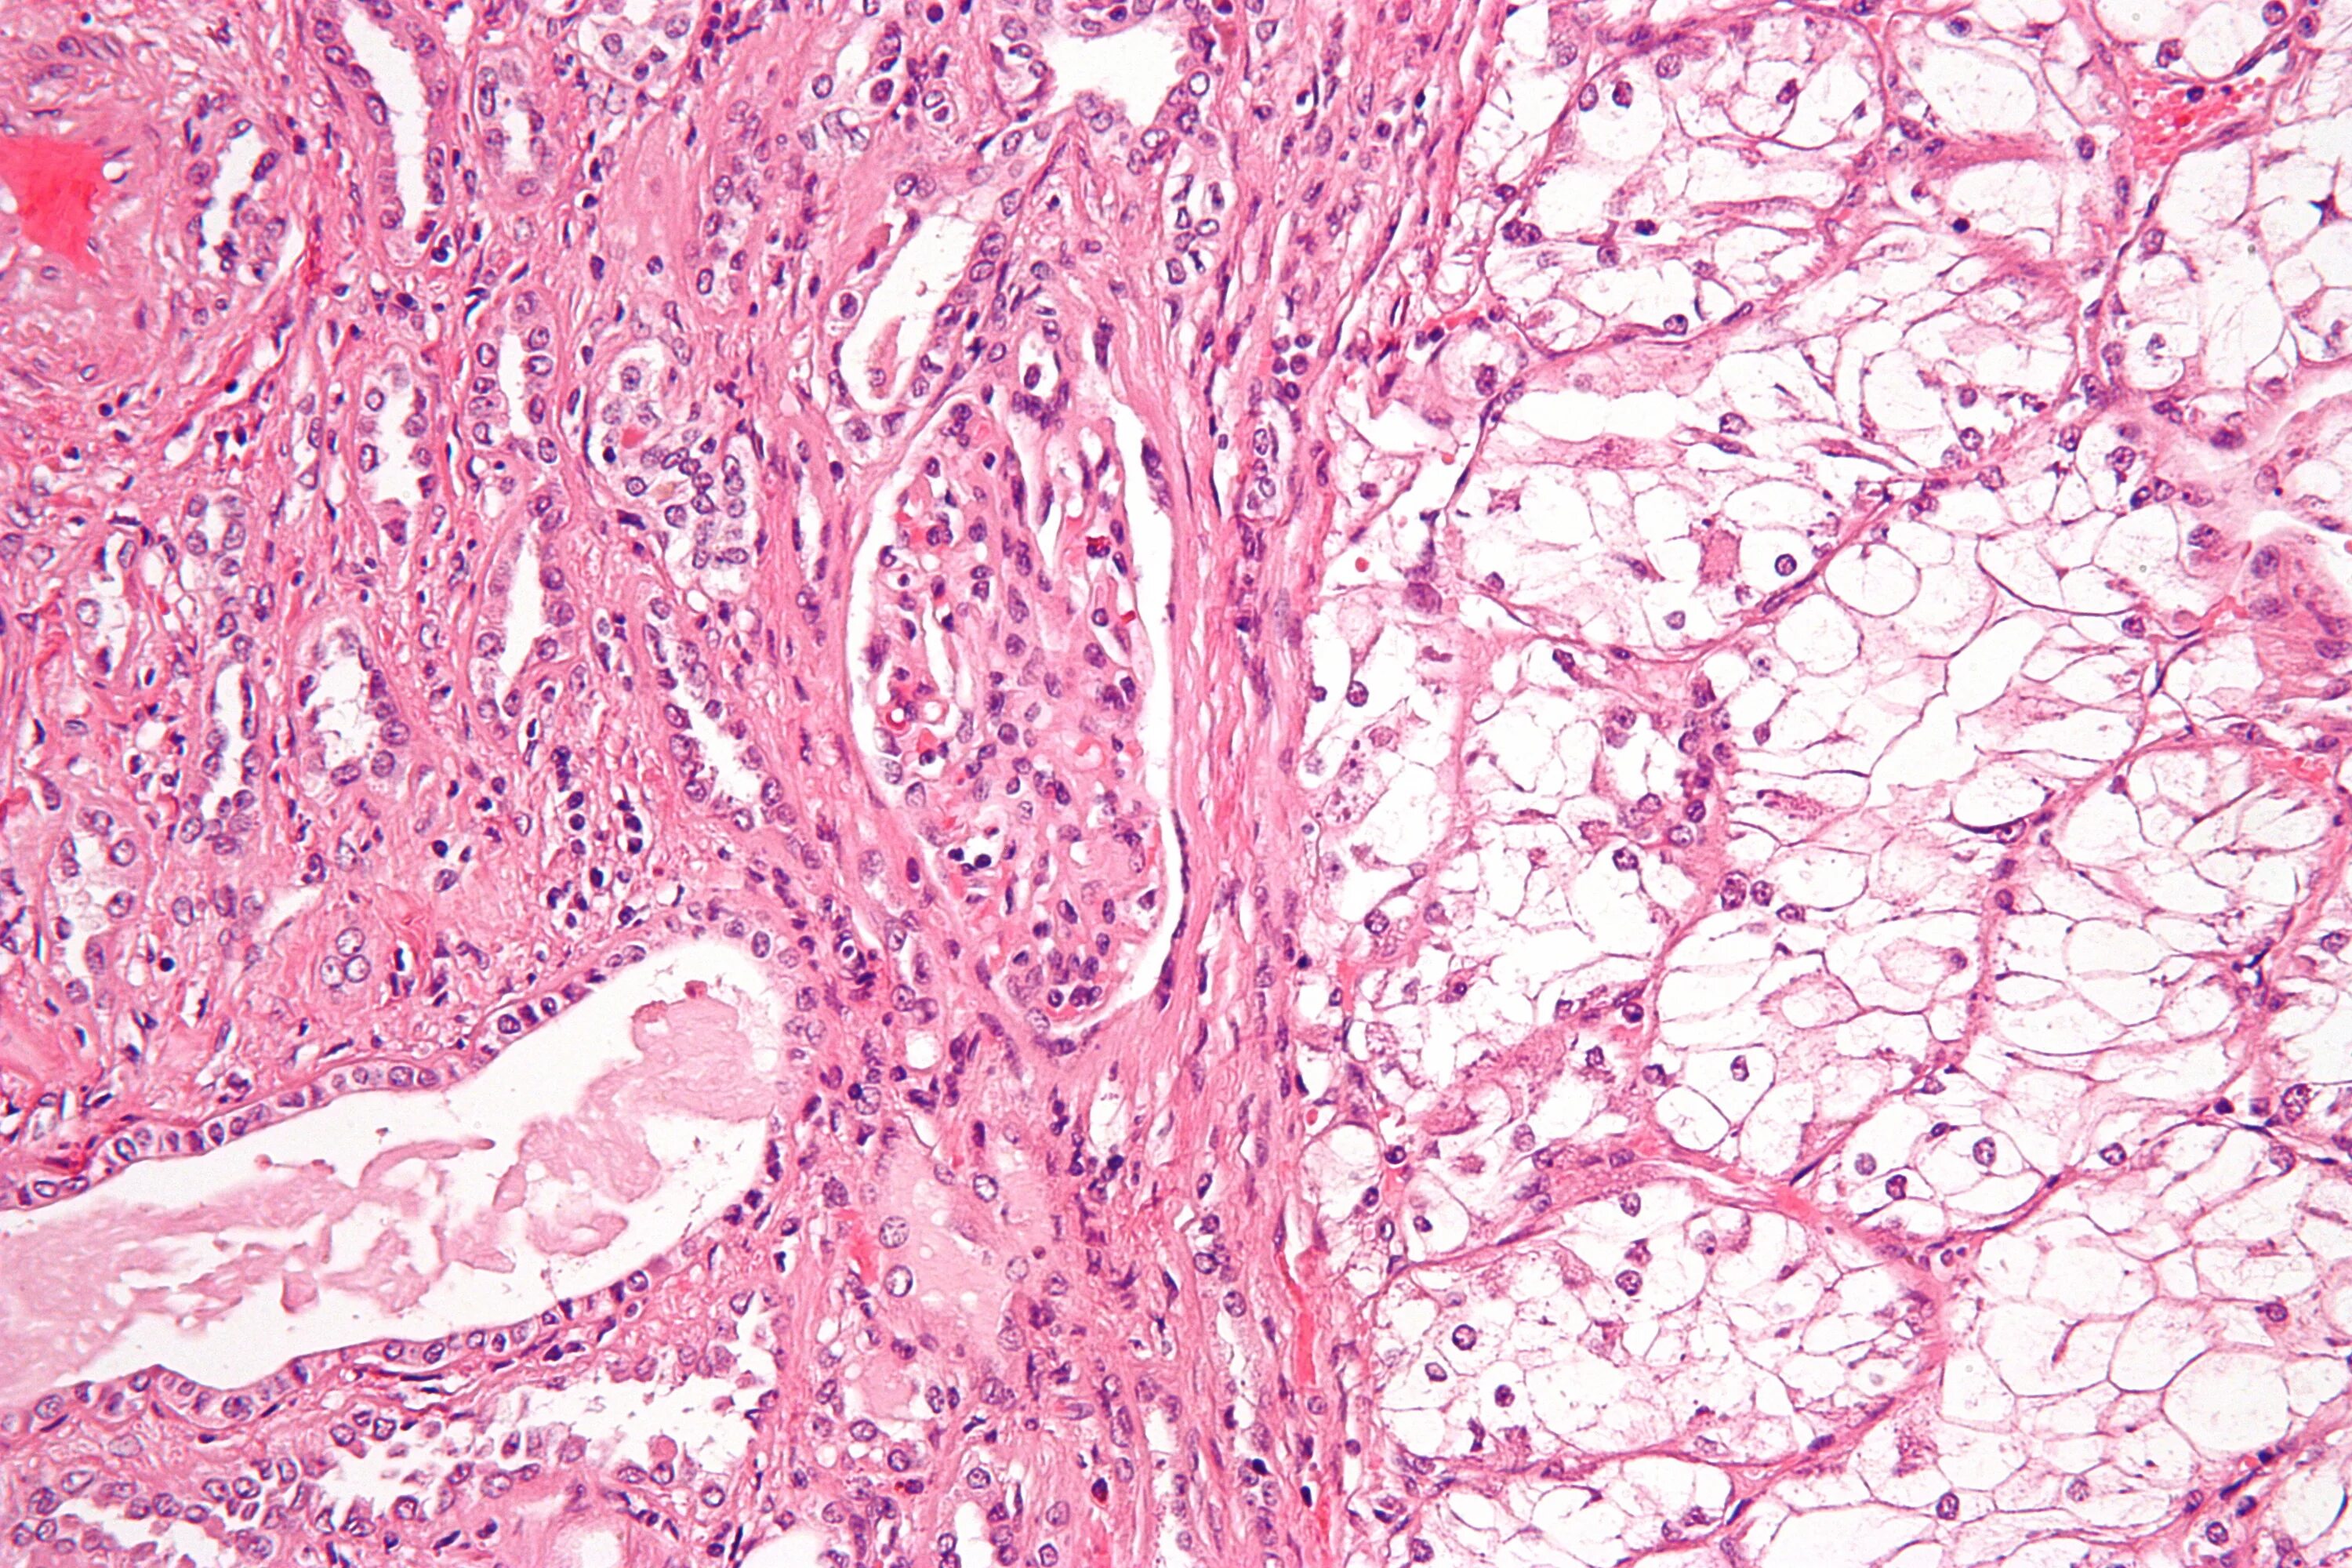

Гистология аденокарциномы